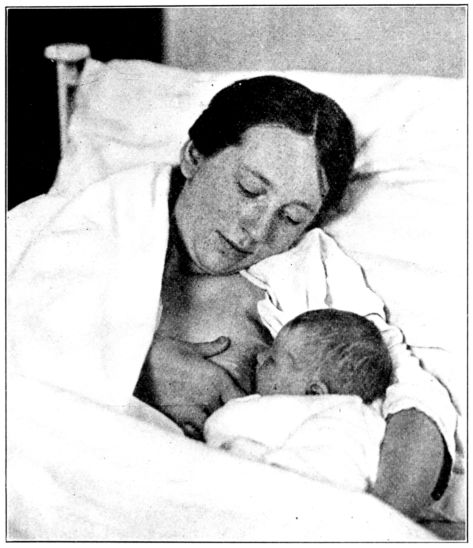

| 138. | Position of mother and baby for nursing in bed | 359 |